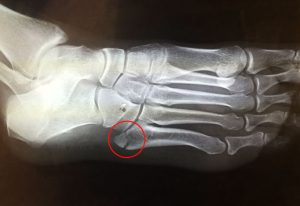

Son fracturas que ocurren generalmente en los pies, producen dolor crónico localizado en un punto, alivian en reposo, aumenta el dolor al caminar o apoyar la zona afectada.

Las fracturas por estrés pueden ocurrir en huesos sometidos a presión constante y repetida, por sobreuso, o micro traumatismos repetidos. Pueden ocurrir en los pies, la rodilla, tibia, peroné, cuello femoral, vértebras, antebrazos etc.